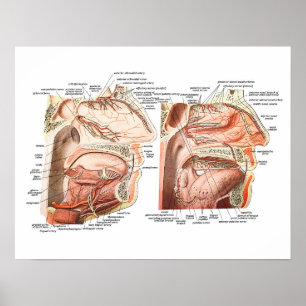

Póster Anatomia interna do rosto humano

Preço45,25 €